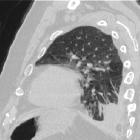

asbestos-related lung and pleural diseases as an endemic exposure in Egypt. A 56-year-old male smoker patient, working in plasters for 13 years, was diagnosed as having round atelectasis for 3 years with a latent period 10 years. Axial CT scan lung window showing left lower lobe subpleural soft tissue density with comet tail sign and underlying pleural thickening denoting round atelectasis